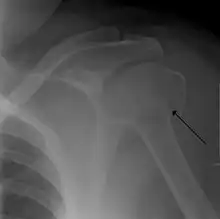

Distal

Distal humerus fractures usually occur as a result of physical trauma to the elbow region. If the elbow is bent during the trauma, then the olecranon is driven upward, producing a T- or Y-shaped fracture or displacing one of the condyles.[7]

Definitive diagnosis of humerus fractures is typically made through radiographic imaging. For proximal fractures, X-rays can be taken from a scapular anteroposterior (AP) view, which takes an image of the front of the shoulder region from an angle, a scapular Y view, which takes an image of the back of the shoulder region from an angle, and an axillar lateral view, which has the patient lie on his or her back, lift the bottom half of the arm up to the side, and have an image taken of the axilla region underneath the shoulder.[9] Fractures of the humerus shaft are usually correctly identified with radiographic images taken from the AP and lateral viewpoints.[12] Damage to the radial nerve from a shaft fracture can be identified by an inability to bend the hand backwards or by decreased sensation in the back of the hand.[5] Images of the distal region are often of poor quality due to the patient being unable to extend the elbow because of pain. If a severe distal fracture is suspected, then a computed tomography (CT) scan can provide greater detail of the fracture. Nondisplaced distal fractures may not be directly visible; they may only be visible due to fat being displaced because of internal bleeding in the elbow.[7]

Fractures of the humerus are classified based on the location of the fracture and then by the type of fracture. There are three locations that humerus fractures occur: at the proximal location, which is the top of the humerus near the shoulder, in the middle, which is at the shaft of the humerus, and the distal location, which is the bottom of the humerus near the elbow.[9] Proximal fractures are classified into one of four types of fractures based on the displacement of the greater tubercle, the lesser tubercle, the surgical neck, and the anatomical neck, which are the four parts of the proximal humerus, with fracture displacement being defined as at least one centimeter of separation or an angulation greater than 45 degrees. One-part fractures involve no displacement of any parts of the humerus, two-part fractures have one part displaced relative to the other three; three-part fractures have two displaced fragments, and four-part fractures have all fragments displaced from each other.[13][14][3] Fractures of the humerus shaft are subdivided into transverse fractures, spiral fractures, "butterfly" fractures, which are a combination of transverse and spiral fractures, and pathological fractures, which are fractures caused by medical conditions.[12] Distal fractures are split between supracondylar fractures, which are transverse fractures above the two condyles at the bottom of the humerus, and intercondylar fractures, which involve a T- or Y-shaped fracture that splits the condyles.[7]